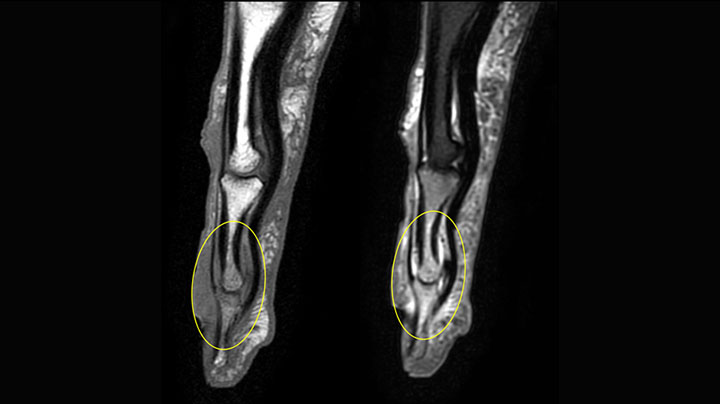

MR-Untersuchung mit Prodiva 1.5T, 72-jährige Patientin mit malignem Melanom am Knöchel. mDIXON TSE bietet eine hervorragende Fettsuppression ohne Verzerrung, wie sie ansonsten bei diesen Extremitäten häufig auftritt.